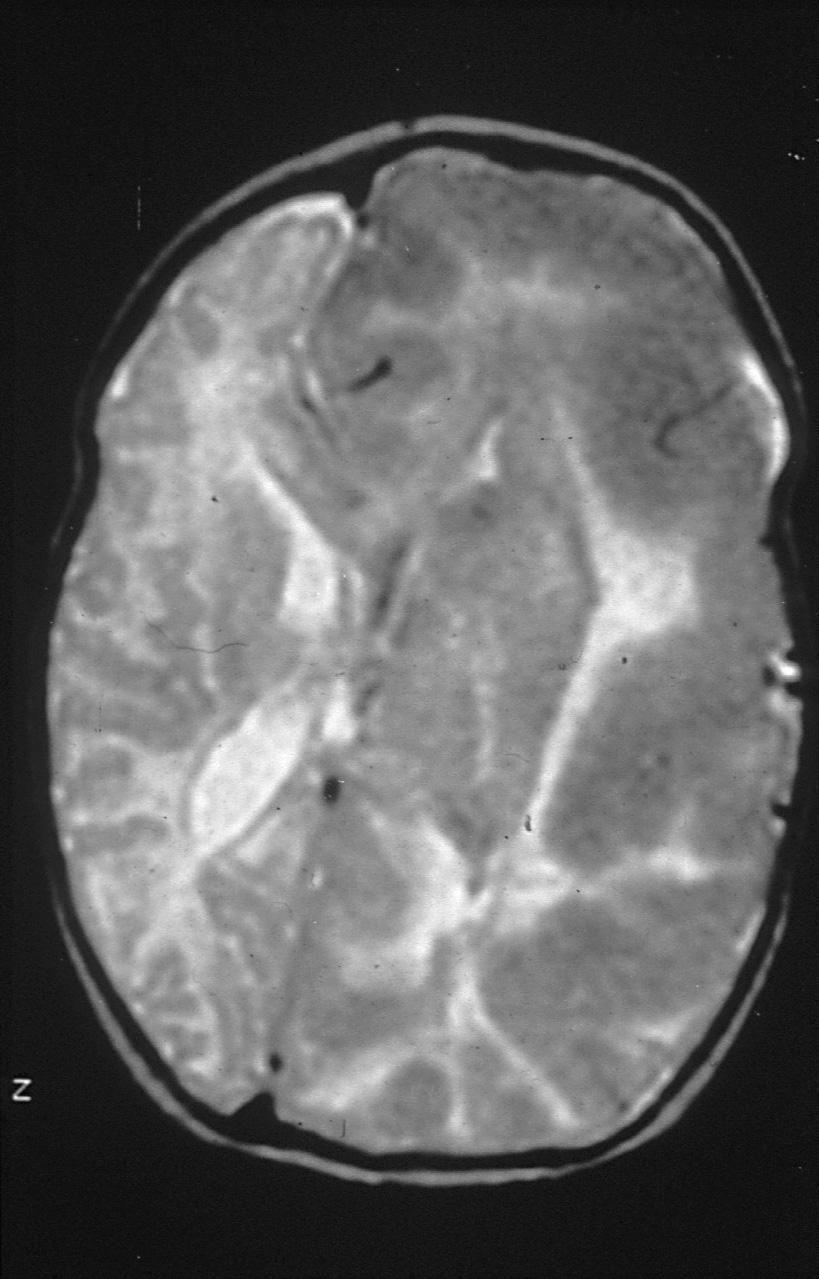

MRI, or magnetic resonance imaging, is a sophisticated medical imaging technique that captures intricate, high-resolution images of various organs and structures within the body. This advanced technology operates using powerful magnets and radio waves, which work together to create detailed visual representations displayed on a computer, allowing radiologist to assess conditions with remarkable clarity.

One of the standout advantages of MRI is its safety profile, as it does not utilize any form of ionizing radiation. This feature makes it an exceptionally safe option for even the youngest patients, including children and infants. For very small children, undergoing an MRI while they are peacefully asleep—often after being fed—can make the experience much easier. Conversely, for older children who may be unable to remain still during the procedure, intravenous sedation or General anesthesia (GA) might be necessary to ensure their comfort and safety.